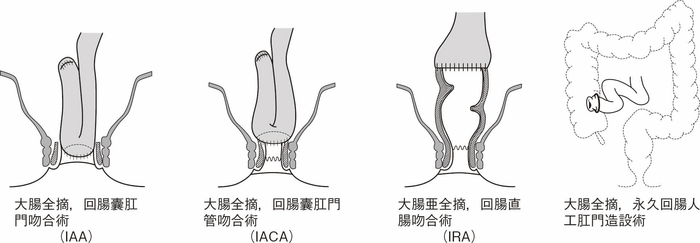

図12 Non-polypoid lesionの内視鏡所見

- 白色光観察

- インジゴカルミン散布像:境界がより明瞭に認識できる。

- 酢酸インジゴカルミン混合液(AIM)散布像:病変全体と周辺粘膜とのコントラストが明瞭となる。

- NBI非拡大観察像:非拡大においても境界の認識は比較的容易となる。

- NIBI拡大観察像:病変中心部では拡張した血管を認める。

- クリスタルバイオレット染色拡大観察像:病変中央では大腸不動の拡張したpitを認める。gの病変辺縁ではpit構造の違いにより周辺粘膜と病変の境界が認識できる。